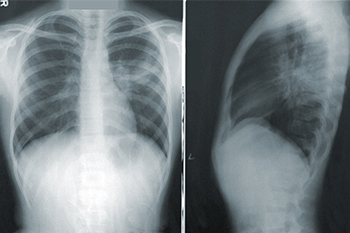

주요 임상 증상은 극도의 호흡 곤란, 무호흡 및 저호흡, 청색증, 발한, 다량의 흰색 또는 분홍색 거품성 가래가 있는 발작 기침, 폐의 대칭적 습식(뾰루지 또는 나비 모양)을 보여주는 X-선 및 흉부 방사선 사진 등으로 나타납니다. 초기 동맥혈 가스 분석에는 낮은 O2, 낮은 CO2 분압, 심한 O2 결핍, 이산화탄소 보유 및 혼합 산증이 포함될 수 있습니다. 폐부종 증

X-선은 주로 흐려지고 증가된 폐 혈관조직, 두드러지고 불분명한 그림자, 폐광 투과율 감소 및 폐 전단 간격 확대로 나타납니다. 흉막에 수직으로 흐르는 컬리 B(Kerley B)선은 두 개의 폐의 하부 늑골 다이어프램 각도 영역에서 볼 수 있으며, 때로는 상부 폐가 대각선으로 구부러져 있고 컬리 A(Kerley A)선이 컬리 B(Kerley B)선보다 깁니다.

폐포 부종은 주로 치밀한 폐포 그림자로 나타나며, 이는 서로 불규칙하게 병합되는 퍼지 그림자입니다. 확산 분포는 한쪽 또는 하나의 잎으로 제한되거나, 혈관하고 신경이 기관과 접하는 문(hilum)의 양쪽에서 확장되어 전형적인 나비 모양의 그림자로 점차 사라집니다. 때때로 소량의 흉막 삼출이 동반됩니다. 그러나 위에서 언급한 증상은 폐 함량이 30% 이상 증가한 경우에만 발생할 수 있습니다. CT와 MRI 검사는 폐 혼잡과 폐 간질 부종을 정량화하고 심지어 구별 할 수 있습니다.